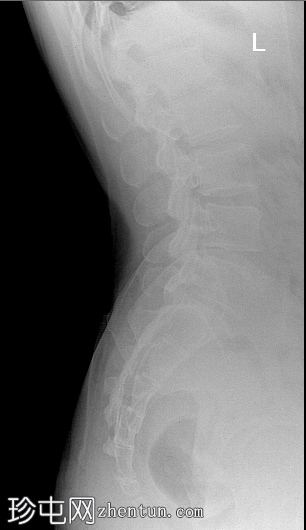

2.png

侧位片

腰椎共6节。L6椎体双侧横突肥大,与骶骨形成假关节,符合腰骶移行椎(Castellvi IIb型)的影像学表现。